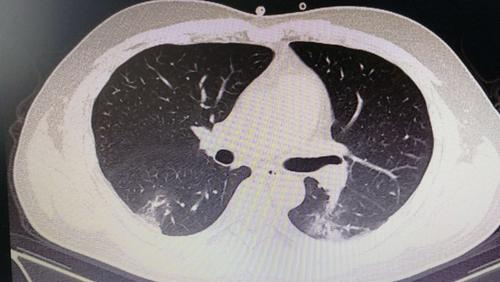

新冠肺炎肺部影像

新冠肺炎肺部影像,新冠肺炎

新冠肺炎的影像学表现小结

因为大众已了解到,新冠病毒感染后肺部ct会出现斑片状磨玻璃影

其它 阅图识病之新冠肺炎一例 写美篇 影像所示: 双肺可见多发大小不